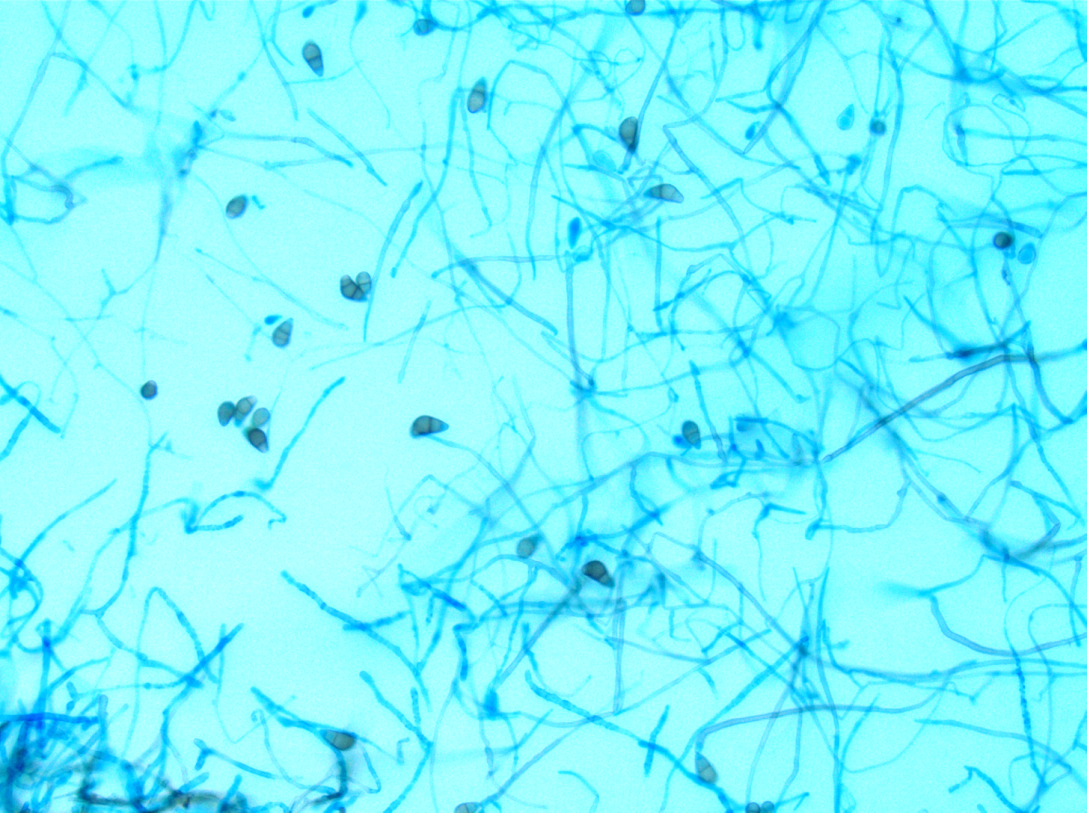

A 41-year-old male was admitted with myasthenia gravis exacerbation and respiratory difficulty. He was diagnosed with myasthenia gravis in 2004, underwent a thymectomy in 2010, and was taking prednisone (20 mg daily). He presented to another hospital one month ago with fever, chest pain, and shortness of breath. He was treated with antibiotics and antifungals for pneumonia, along with 5 days of immunoglobulin for a possible myasthenia gravis crisis, but showed no improvement. After admission, a CT scan revealed diffuse bilateral mixed airspace and ground-glass opacities without pleural effusions, most concerning for multifocal pneumonia. A bronchoalveolar lavage (BAL) with Gomori methenamine silver (GMS) staining showed hyphal and yeast elements. Both BAL and urine Histoplasma antigen tests were positive. He was started on posaconazole (300 mg daily), which led to an improvement in symptoms, and he was subsequently discharged. After 6 weeks of culture, macroscopic and microscopic features of the colony confirms Histoplasma capsulatum (Figure 1).

Culturing Histoplasma from clinical specimens is definitive, but it can take 4-8 weeks due to the slow growth of the fungus. The colonies appear white at young growth, have a cottony, cobweblike-aerial mycelium and can mature into brown or grey color on reverse (Figure 1, top) 8. Microscopic examination of mold colony using lactophenol cotton blue preparations reveals the characteristic large, rounded, tuberculate macroconidia (circular structures with roughened/spiked edges) originating from short, hyaline conidiophores (Figure 1, bottom). Histoplasma capsulatum appears as small (2-5 μm), oval, intracellular yeast cells typically found within macrophages. The yeast may exhibit a clear space which may appear like a capsule, but is actually a retraction artifact due to the processing of the specimen. Staining with GMS or periodic acid-Schiff (PAS) highlights the yeasts9. Molecular methods such as PCR and sequencing have been shown to detect cases of Histoplasma as well.